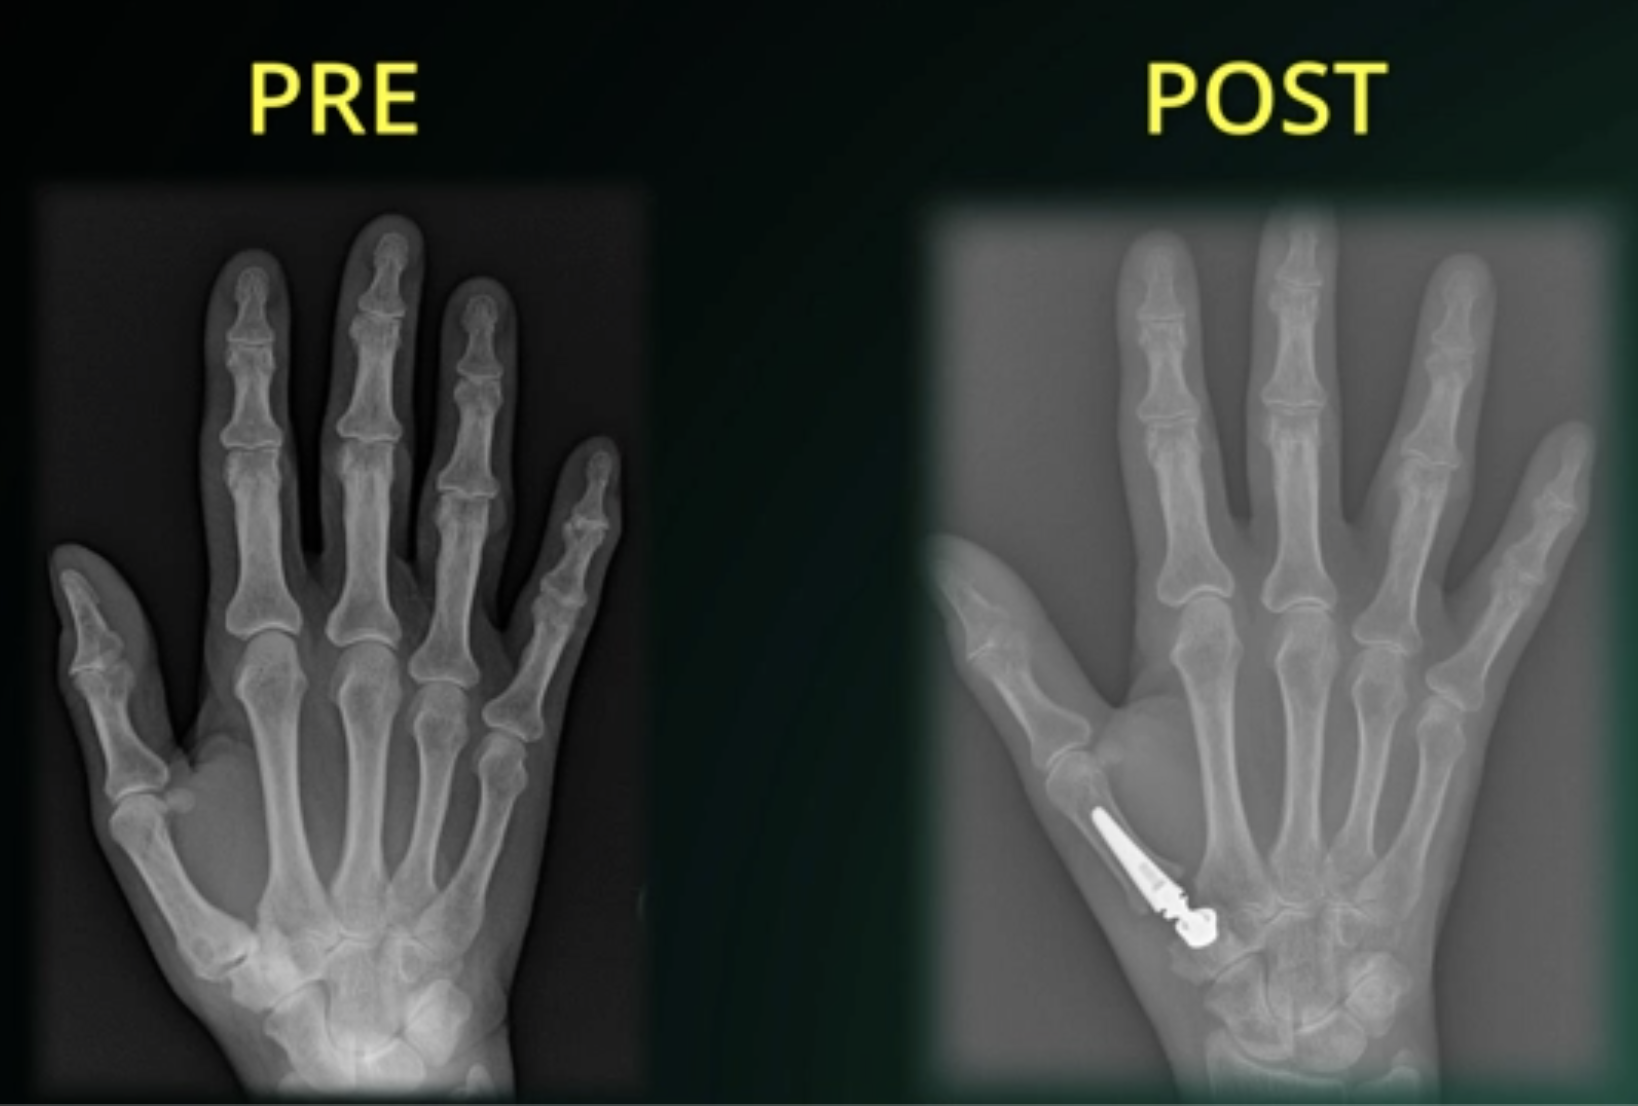

(3) Sostituzione Protesica: L'artroplastica con protesi a doppia mobilità permette un più rapido recupero della motilità e della forza e della regressione del dolore rispetto alle tecniche descritte precedentemente. Anche in questo caso, è necessario indossare bendaggio per la prima settimana post-intervento ed evitare sforzi e carichi per i primi 30gg.

Figura 5 - Immagine radiografica pre e post intervento di sostituzione protesica